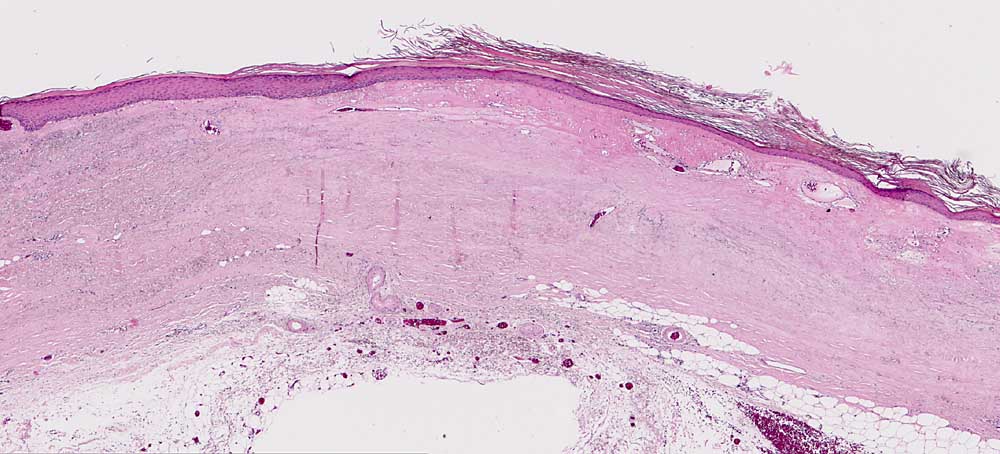

Chronische Radiodermatitis

Diagnose Gruppe

Haut

Haut, Rumpf

Pathologischer Befund